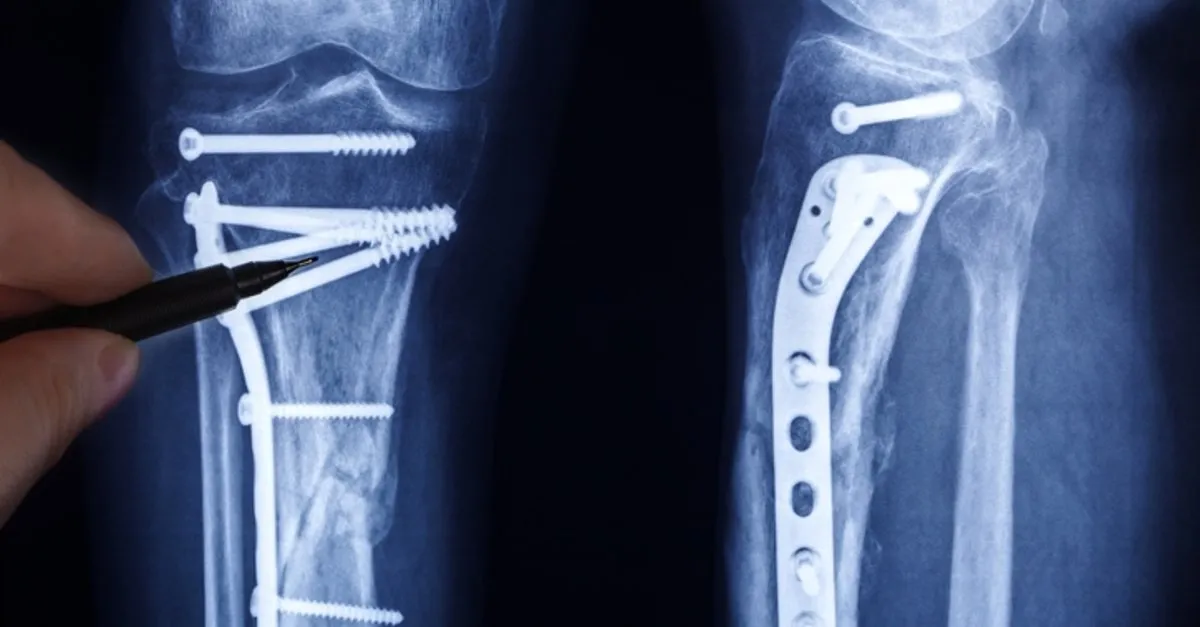

Eklem dejenerasyonuna neden olan kemik eğrilikleri veya dizilim bozukluklarının düzeltilmesi de kireçlenmenin ilerlemesinin durdurulması ve ağrıların kontrolünde etkili olmaktadır. Osteotomi adı verilen bu işlemde kemik kesiler yapılarak eklem pozisyonları tekrar ayarlanır ve yükün dizden anatomik şekilde geçmesi sağlanarak kireçlenmiş bölgedeki baskıyı azaltır. Bu sayede, ağrı ve hareket eklem korunarak sağlanmaya çalışılır. Osteotomi, 60 yaşın altında ve fazla kilolu olmayan, dizin sadece bir tarafında ağrı olan, çoğunlukla aktivite veya uzun süre ayakta durma nedeniyle kireçlenmeye sahip olunan durumlarda uygun olabilir. Dizin tek kompartman kireçlenmesi olan, orta yaşta, aşırı kilolu olmayan ve aşırı eklem deformitesi ile hareket kısıtlılığı olmayan ve iltihaplı eklem romatizması bulunmayan hastalarda unikompartmantal (tek kompartmanı değiştiren) diz protezleri kullanılabilir. Sıklıkla dizin iç kesiminde olan kireçlenmelerde kullanılan bu yöntem eklem dizilimini düzelterek ağrıyı ortadan kaldırır.

İleri evre diz osteoartritinde en sık kullanılan tedavi seçeneği total diz protezidir. 60 yaş üzeri, ileri derecede eklem dejenerasyonu olan ve eklemde eğriliği olan hastalarda hareket kısıtlılığı ve ağrının giderilmesindeki en etkili yoldur. Dejenere olan eklem dokusu ve kemiğe yapılacak uygun osteomiler (kemik kesileri) ile eklemin bağları korunarak yapay bir diz eklemiyle eklem tekrar oluşturulur. Hastanın ertesi gün yürümeye ve aktif rehabilitasyona başlayabilir ve birkaç gün içinde taburcu olur. Genellikle minimal invaziv cerrahi teknikleri uygulanır. Son yıllarda robotik diz protezi uygulamaları ile hastanın kendi anatomisine daha uygun protez uygulamaları da yaygınlaşmaya başlamıştır.